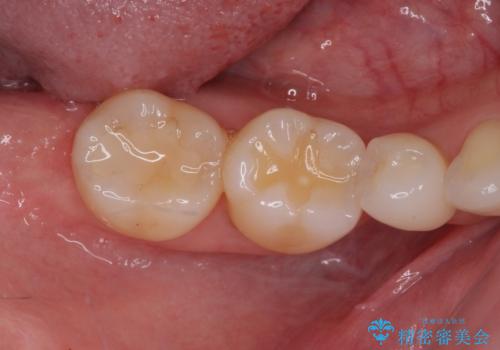

右下の欠損分は奥歯が倒れ込んでスペースがなくなっていたため、矯正治療により本来の位置に歯を移動させ、オールセラミックブリッジによる欠損補綴治療を行うこととしました。

右下は移動量が多いため、十分な移動が達成されない場合はワイヤー装置を使用する予定としておりましたが、しっかりとマウスピースを装着してくださったため、前歯とともに十分に歯を動かすことができました。